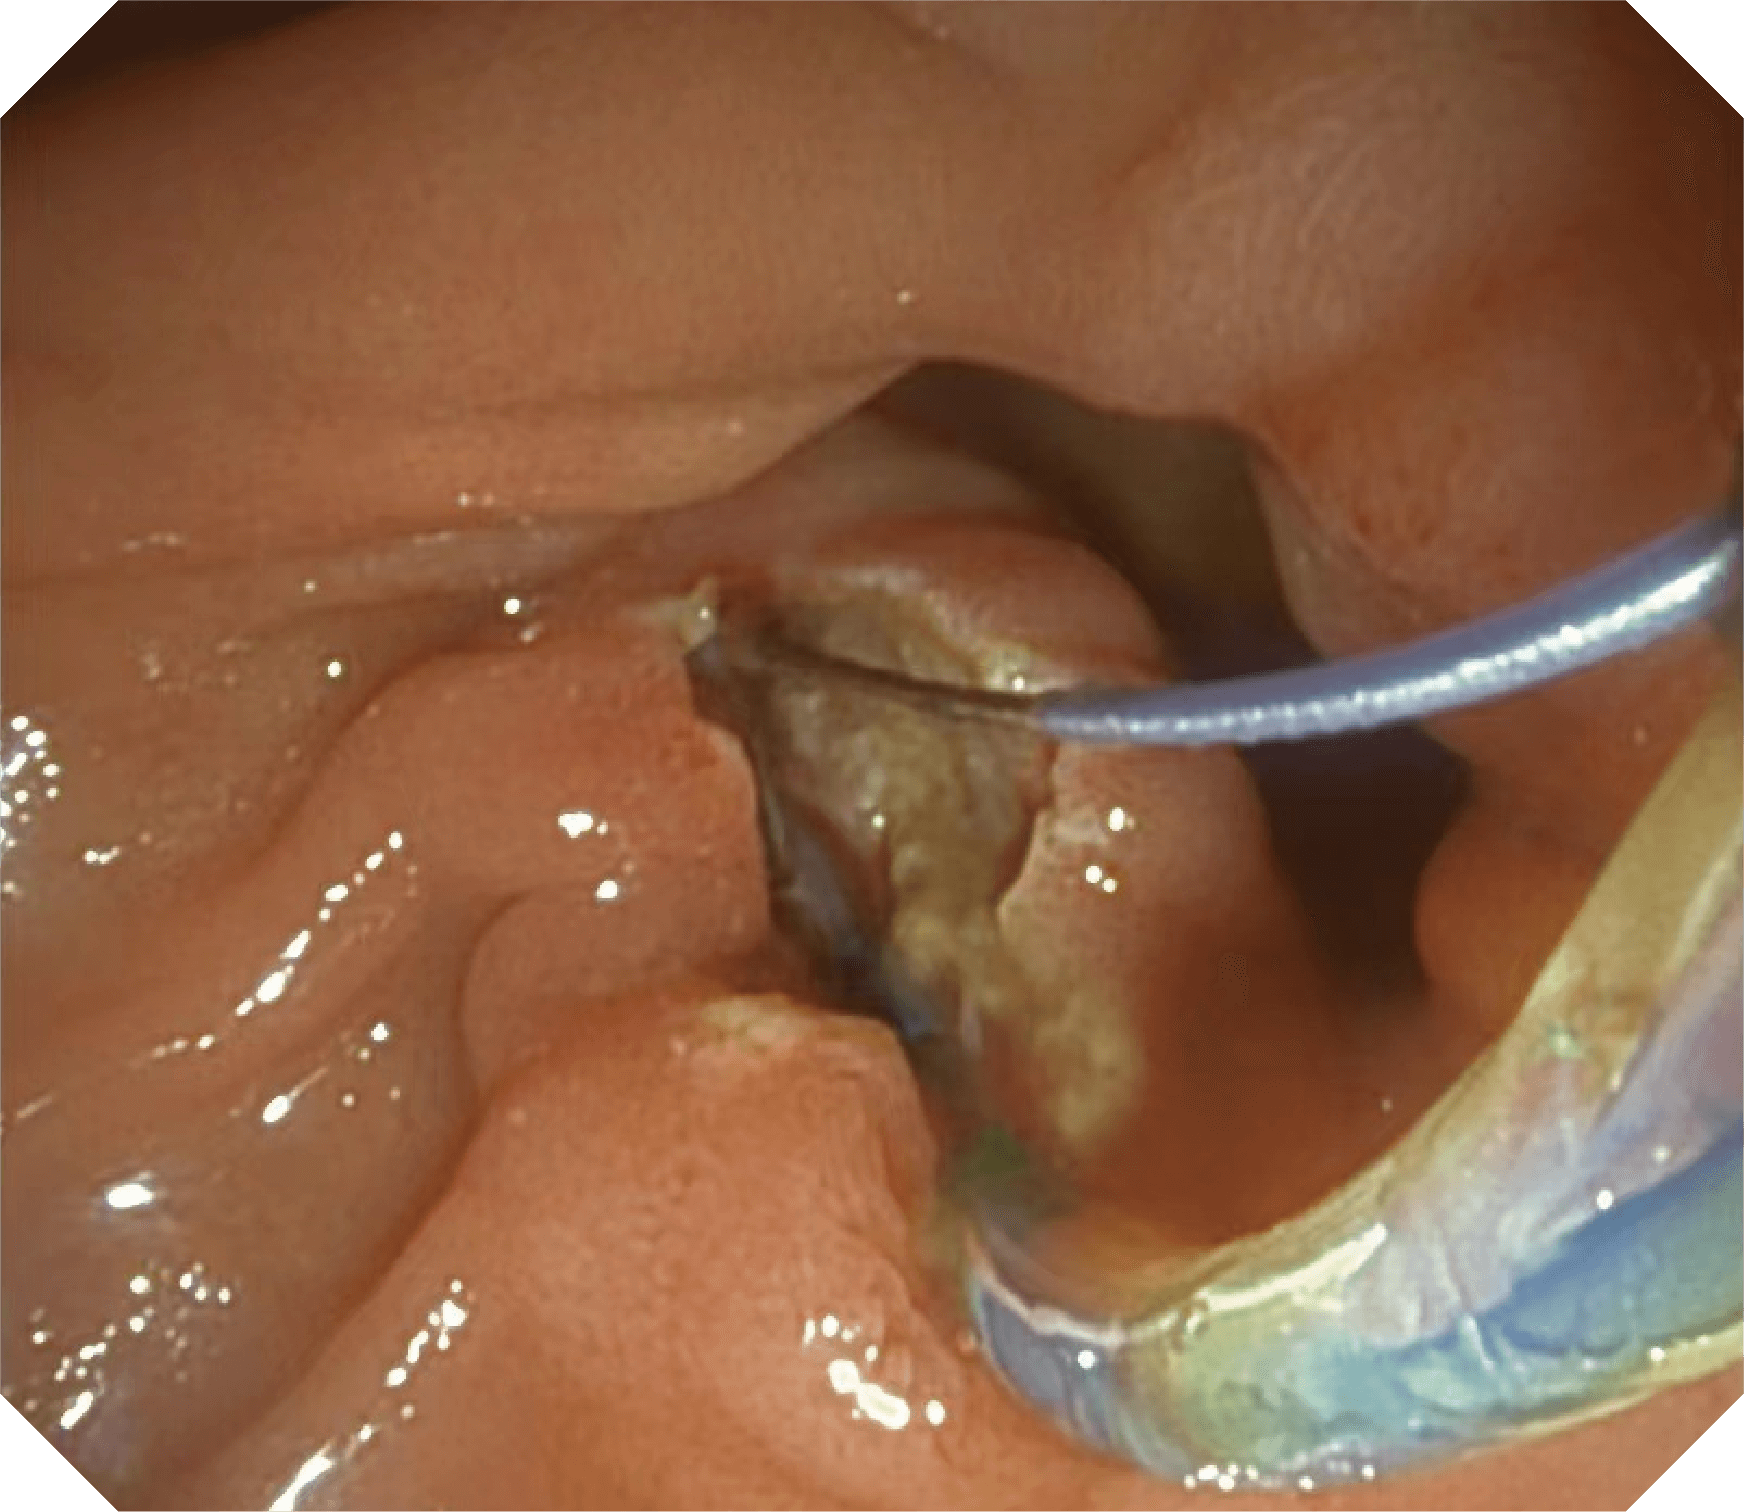

4.2mm大钳道,器械交换更顺畅

导丝机械锁紧功能

V槽设计提升导丝控制

优异的手术器械抬举性

更好的通过性,更稳定的镜体支撑力